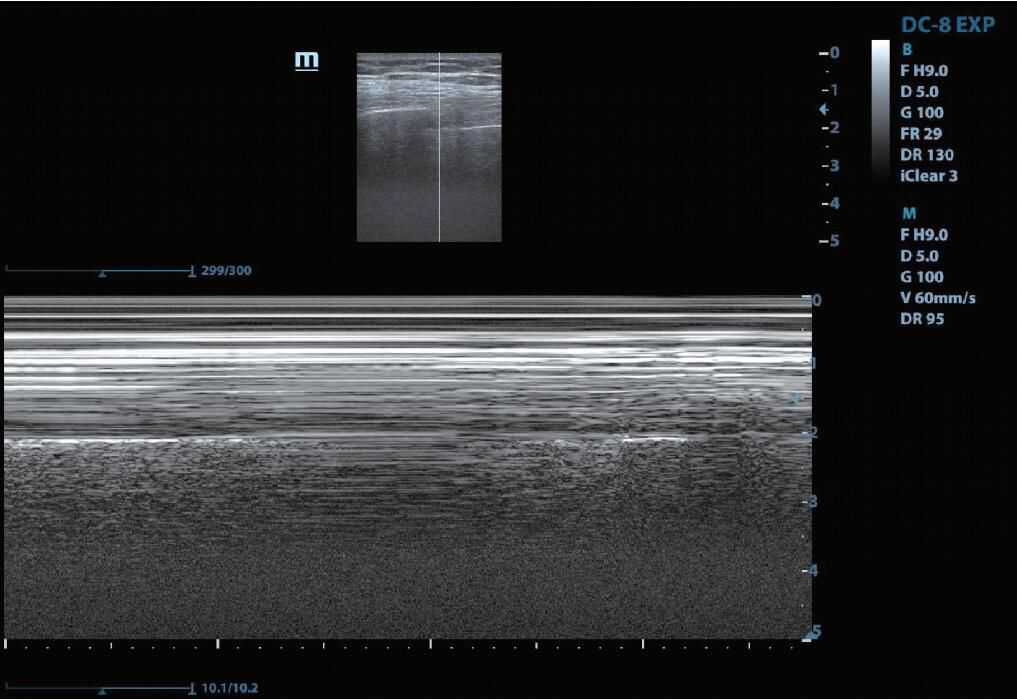

3.M模式探头在某一位置上反复发射、接收信号,用纵坐标表示目标结构的移动深度,横坐标表示时间,通常用于观察瓣膜运动或测量胎儿心脏活动(图2)。

图2M模式